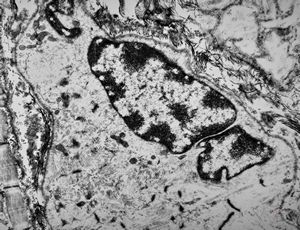

M,56y. | amyloidosis - tendon